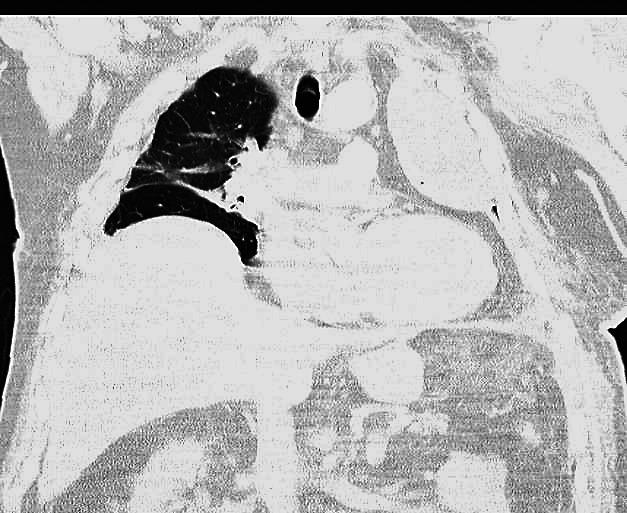

Blunt chest trauma is an important cause of morbidity and mortality in traumatized emergency patients. We report the case of a 74-year-old man who suffered a glenohumeral joint dislocation, trans trochanteric femur fracture, multiple rib fractures, diaphragmatic rupture with chest herniation of the spleen and stomach associated with herniation of the lung through an anterior chest wall defect after blunt trauma. Although immediate surgical repair was performed, he developed a delayed complication of multiple rib fracture in the form of large extrapleural hematoma that had to be surgically removed. Due to massive pulmonary contusion and prolonged pulmonary collapse, we used surfactant to facilitate alveolar opening after evacuation of the hematoma.

钝性胸部创伤是创伤急诊患者发病率和死亡率的重要原因。我们报告了 1 例 74 岁男性患者,该患者因钝性创伤导致肩关节脱位、转子下股骨骨折、多处肋骨骨折、横膈破裂,脾和胃通过前胸壁缺损疝入胸腔,同时肺疝出。尽管立即进行了手术修复,但他出现了多发肋骨骨折的迟发性并发症,表现为巨大的胸腔外血肿,需要手术清除。由于严重的肺挫伤和长时间的肺不张,我们在清除血肿后使用表面活性剂促进肺泡开放。